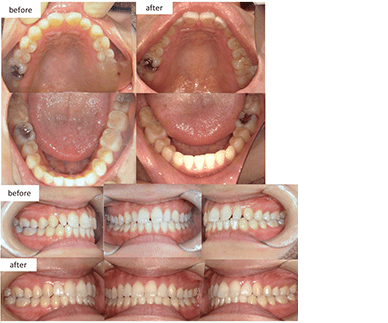

治療方法 上下床矯正装置+インビザライン

(親知らず抜歯)治療の説明 主訴: 右上1と右下1が出ている、叢生 年齢 23歳 ![]()

治療費用 877,800円(税込)

(インビザライン767,800円 床矯正2装置110,000円)治療期間 3年1ヶ月 通院回数 18回 治療の副作用(リスク) 咬合痛、歯根吸収、歯根露出が生じる可能性があります。 歯科医師からのコメント 上下で拡大床装置ありで期間は3年ですが、右上1番の唇側傾斜が改善、しっかり噛めるようになっています。 本人許可 症例写真としてのHPなどへの掲載許可を得ています。